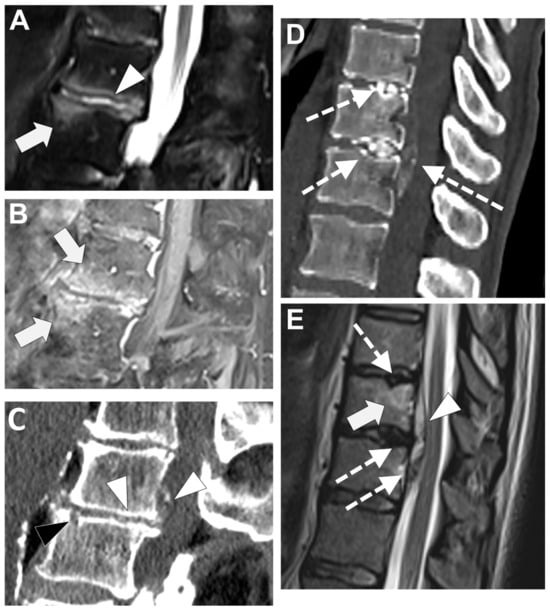

In Figure 6 an exemplificative case of TbS is presented.

Figure 6. Tubercular spondylodiscitis. A 24-year-old man of Sudanese origin presented with thoracic and lumbar pain evolving for several months. An MRI was performed with (A) T2-weighted imaging (WI) and (B) contrast-enhanced (CE) T1-WI, as well as a CT-scan in bone kernel (C) and abdominal kernel after contrast medium injection (D,E). It demonstrates preserved disk but extensive sub ligamentous collections spreading along the anterior side of the thoracic and lumbar vertebral bodies (white arrowhead), but also along the posterior vertebral collateral ligament (white arrows) with large anterior and posterior erosions (black arrows). Please note the extensive collections spreading in the presacral space and along bilateral iliopsoas muscles without surrounding inflammation (white dashed arrows).